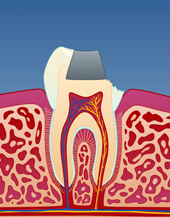

Bildet viser at en tyggeknute til en tann i overkjeven har frakturert. Tannen var svekket på grunn av en stor amalgamfylling.